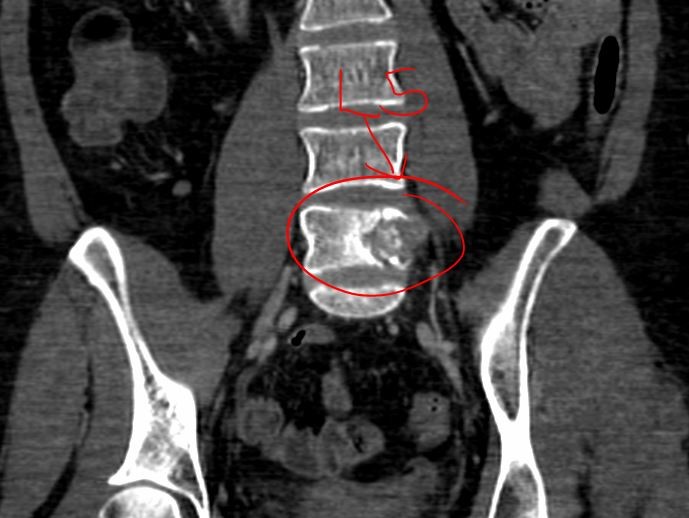

Two years later (2020) and 3 months after finishing her last blockage treatment for the adenocarcinoma (October) a new diagnosis has determined that the previous treatment failed and now Anabella must face the fact that the cancer has spread to 1 vertebra of her spine and 2 more nodes on the right side of the affected breast.